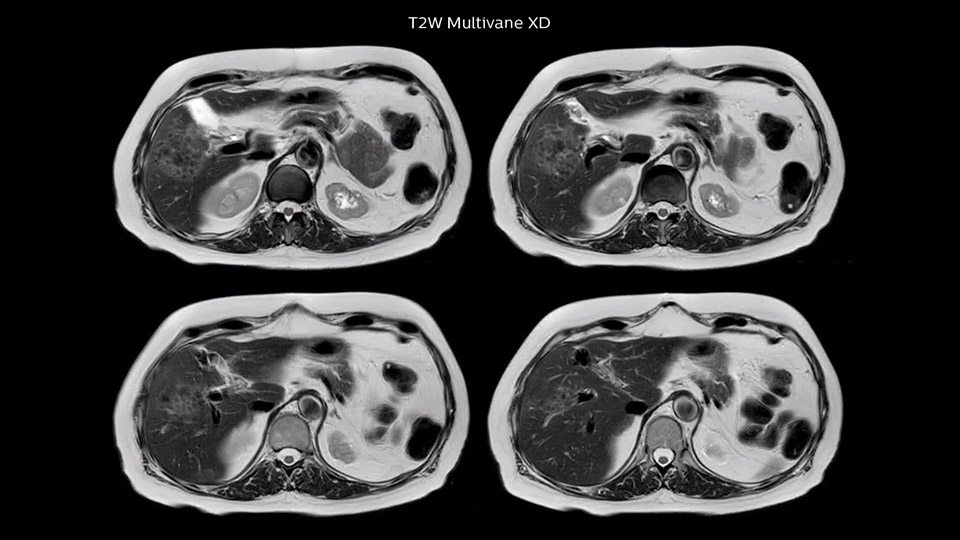

Comparison of liver MRI with and without MultiVane XD motion correction

In this example the image quality of the MultiVane XD images is evidently better than in the images without MultiVane XD. Ingenia 1.5T with dS Torso coil solution.